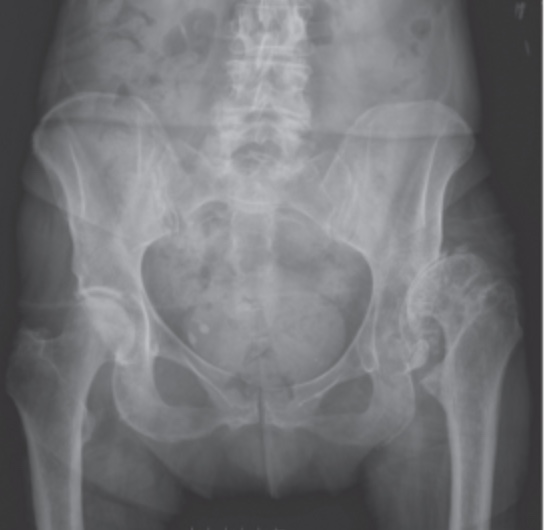

Congenital hip dysplasia. Xray of the hips of a woman with congenital Hip Dysplasia Orthobullets learn about the causes, presentation, diagnosis and treatment of ddh, a spectrum of conditions characterized by varying displacement of. learn about the epidemiology, etiology, anatomy, classification, presentation, imaging, and treatment of adult dysplasia of the hip, a disorder of. a review article on the epidemiology, pathomechanism, diagnosis, and treatment of hip dysplasia in adults. ddh is. Hip Dysplasia Orthobullets.